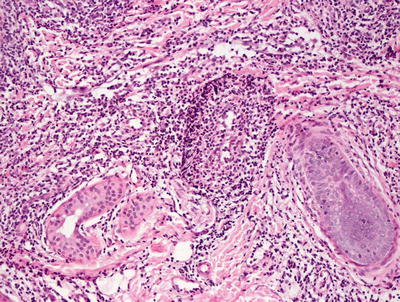

3.8.2 Histology

The histologic findings in hydroa vacciniforme are not specific. The epidermis is markedly spongiotic in early lesions, progressing to reticular degeneration and ultimately necrosis in later stage lesions (Fig. 3.17). Within the dermis, there is a brisk infiltrate that consists predominantly of lymphocytes and histiocytes (Figs. 3.18 and 3.19). Eosinophils are not abundant. Neutrophils may be observed in ulcerated lesions, but this is likely a secondary phenomenon.

Fig. 3.17

Hydroa vacciniforme demonstrates a subepidermal blister with abundant dermal edema and a brisk inflammatory infiltrate

Fig. 3.18

A brisk inflammatory infiltrate in the dermis extends into the overlying epidermis in hydroa vacciniforme. Blister formation is due to spongiosis and can be at any level

Fig. 3.19

Hydroa vacciniforme is characterized by a brisk superficial and often deep dermal inflammatory infiltrate